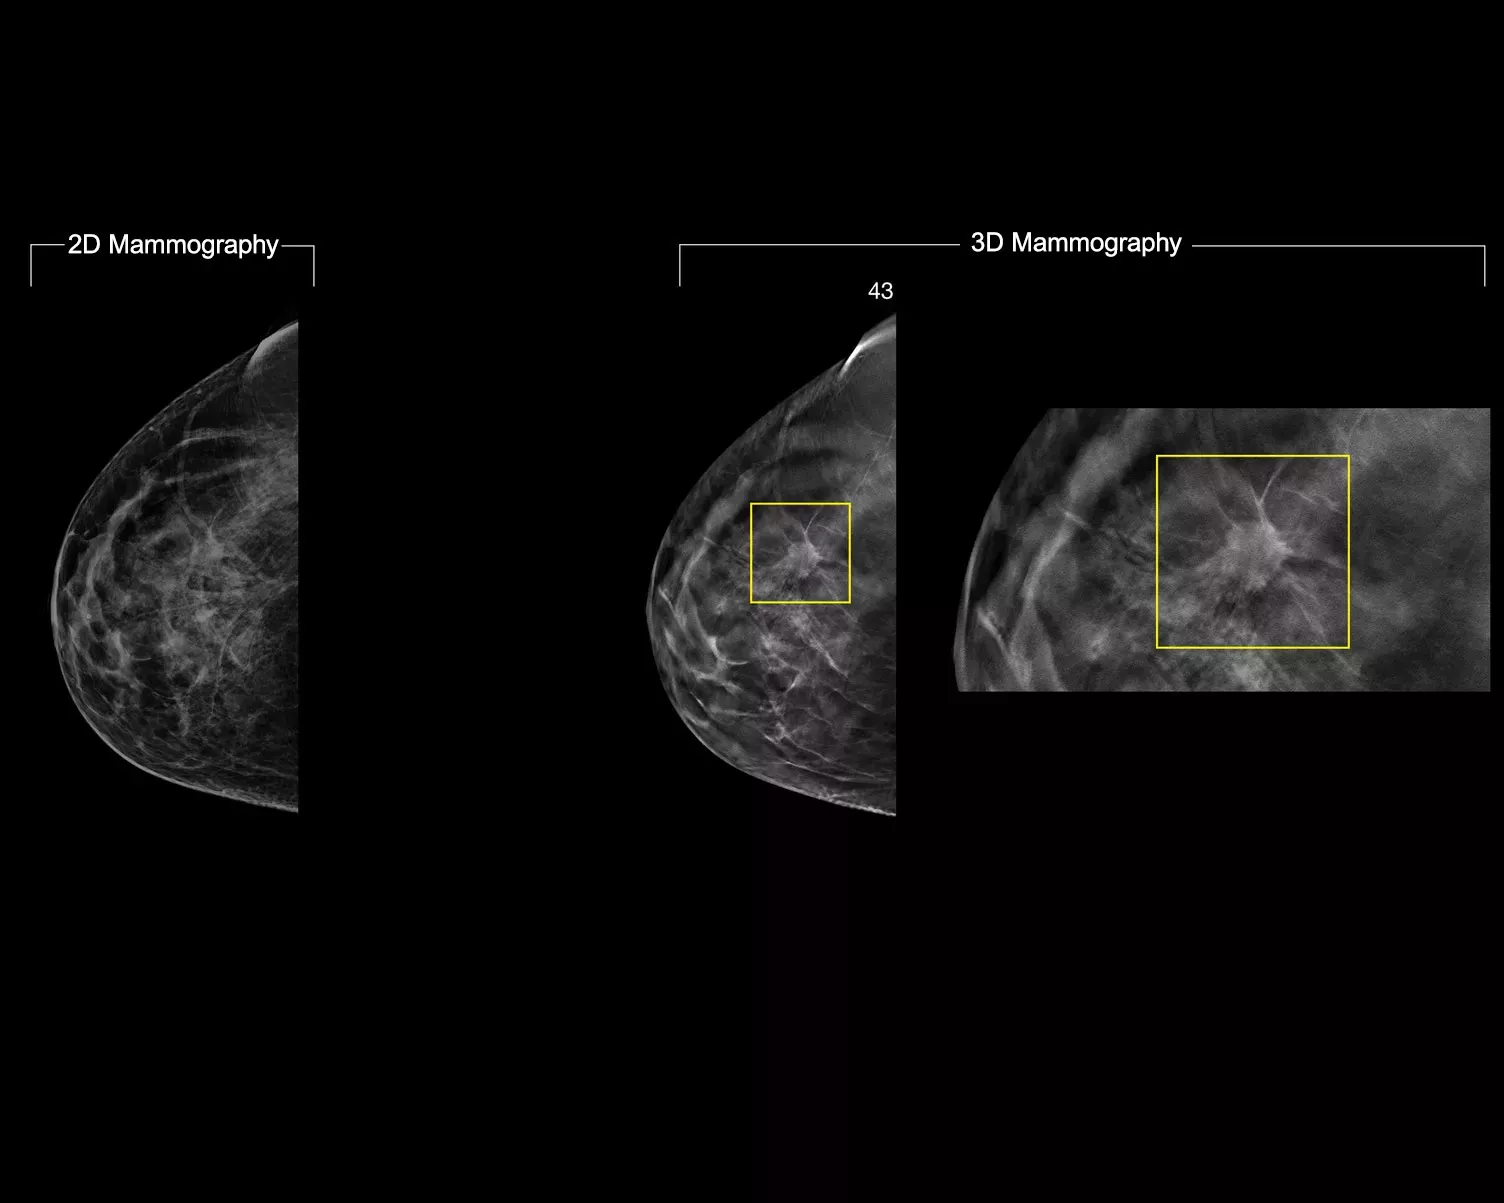

3DQuorum-teknik använder Genius AI™-drivna analyser för att på ett unikt sätt rekonstruera högupplösta 3D Mammography™-data för att ge 6 mm SmartSlices. Den påskyndar granskningstiden genom att minska antalet bilder som ska granskas utan kompromisser gällande bildkvalitet, sensitivitet eller exakthet.2, 3 Med vår nyaste innovation kan du minska granskningstiden med en timme om dagen.2, 3*

Genius AI-analyser identifierar intresseområden och bevarar viktiga funktioner under skapandet av SmartSlices.2 6 mm SmartSlices med överlappning på 3 mm säkerställer att inga data förloras och att bläddringen fortsätter utan avbrott.4–6

Vid granskning av SmartSlices i stället för 1 mm-snitt minskas antalet 3D™-bilder att granska med två tredjedelar.4–6 Detta sparar i genomsnitt en timmes bildtolkningstid per dag.3

3DQuorum-teknik använder Genius AI-driven analys för att generera SmartSlices och påskynda granskningstiden genom att minska antalet bilder som ska granskas. Inga kompromisser görs när det gäller bildkvalitet, sensitivitet eller exakthet.4, 5